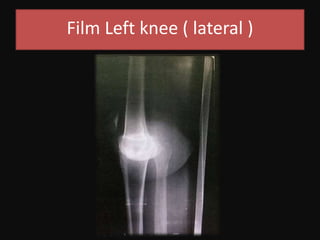

Film Left knee ( lateral )

Film Left knee( lateral )